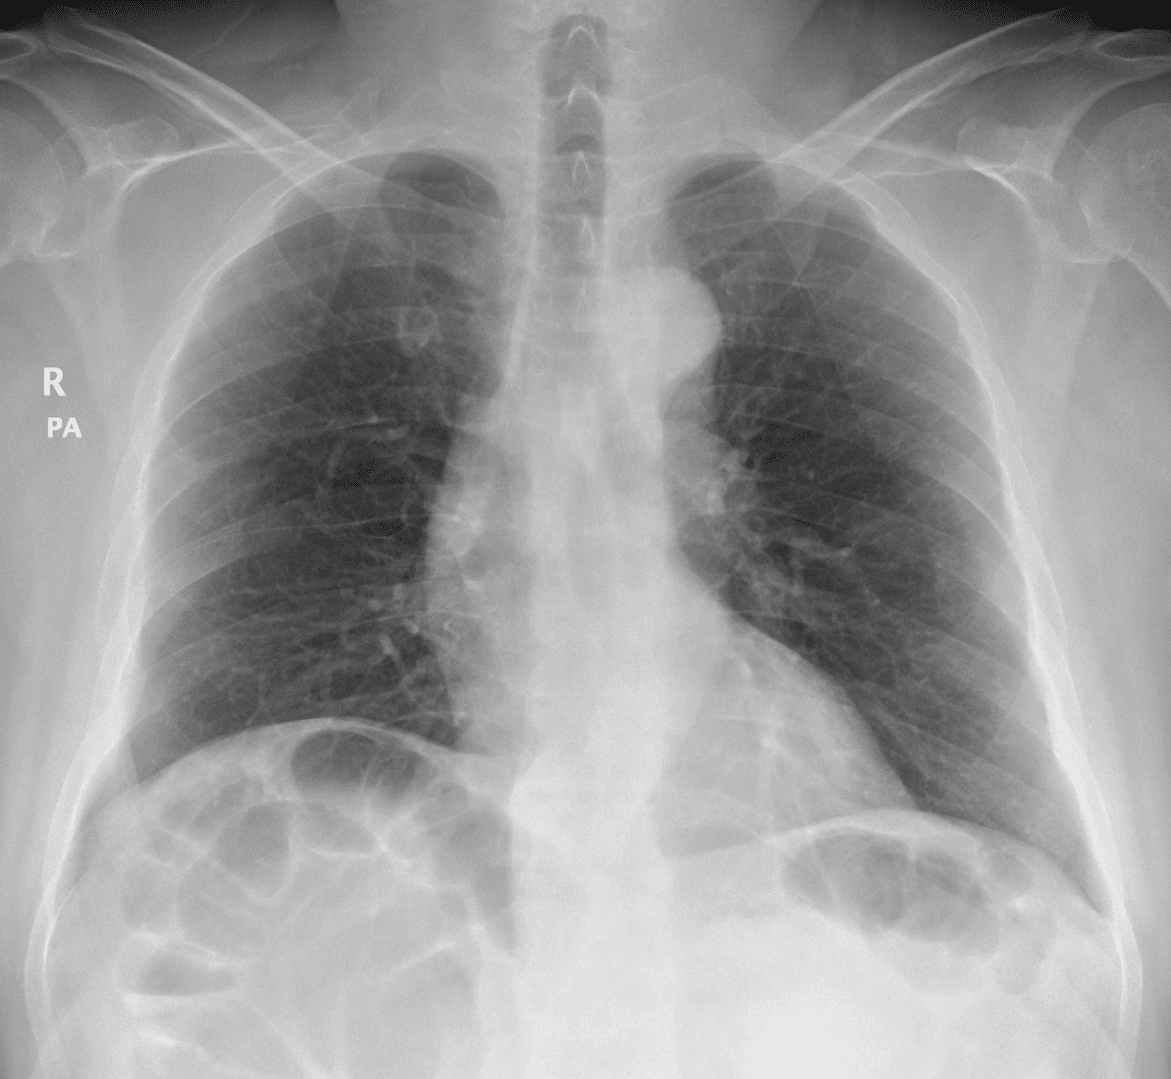

Chilaiditi

» Thông tin: Nam giới – 48 tuổi.

» Lâm sàng: Đau mạn sườn phải 1 tháng.